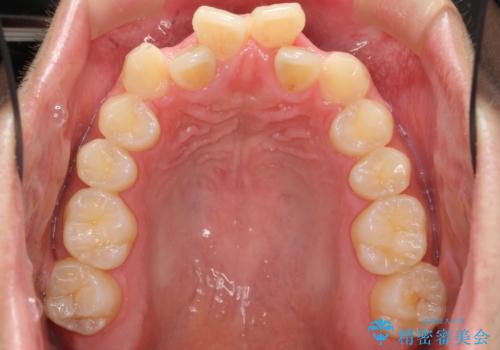

下の前歯が3本になり奇数になることで、上下の真ん中は一致しませんが、そこまで目立たないと思います。

上の前歯のガタガタも、わずかに歯を削って並べていますので、出っ歯になったりしないようにしています。